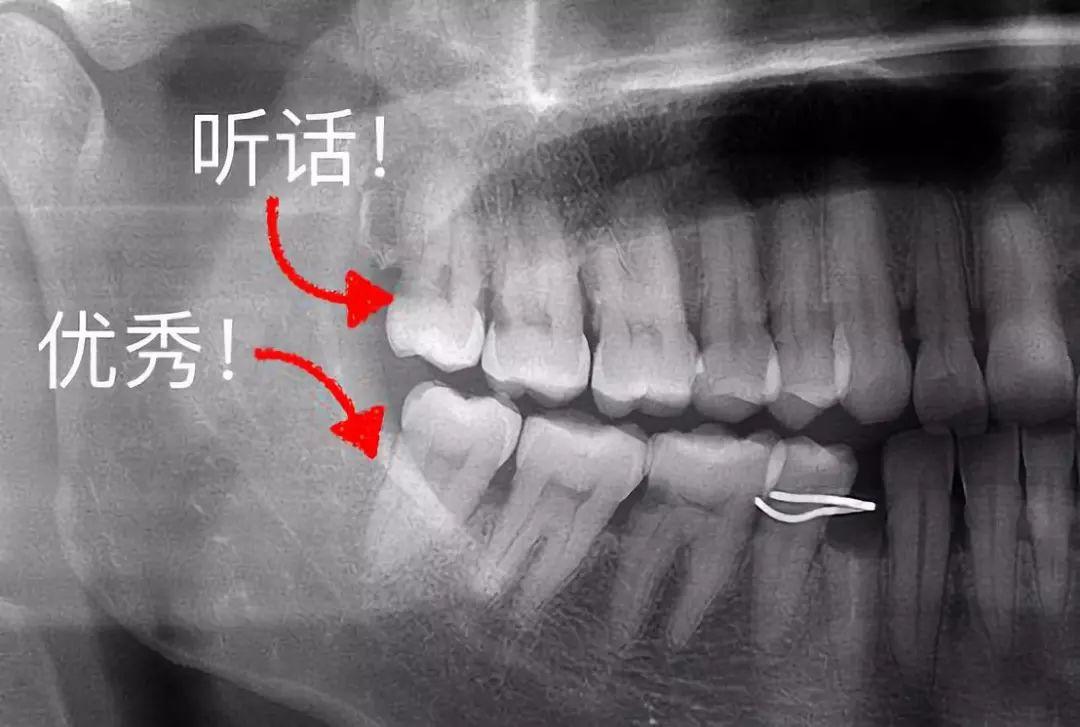

3、這些「聽(tīng)話(huà)」的智齒不用拔

有一些特別乖的智齒,整整齊齊長(zhǎng)出來(lái),上下可以咬合,也沒(méi)有什么蛀牙,平時(shí)都能刷干凈。那么,這種、聽(tīng)話(huà)的智齒完全可以留下,成為咀嚼食物的工具。

整齊、正位萌出的智齒

▍來(lái)源:何劍亮醫(yī)生